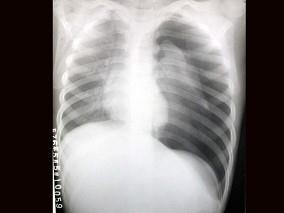

问题 患者,男,3岁,突发左侧胸痛伴呼吸困难3小时入院,如图所示,最可能的诊断为?(?)

选项 A.左侧肺气肿 B.左侧气胸 C.左肺门淋巴结结核 D.右肺小叶性肺炎 E.以上都不正确

答案 B